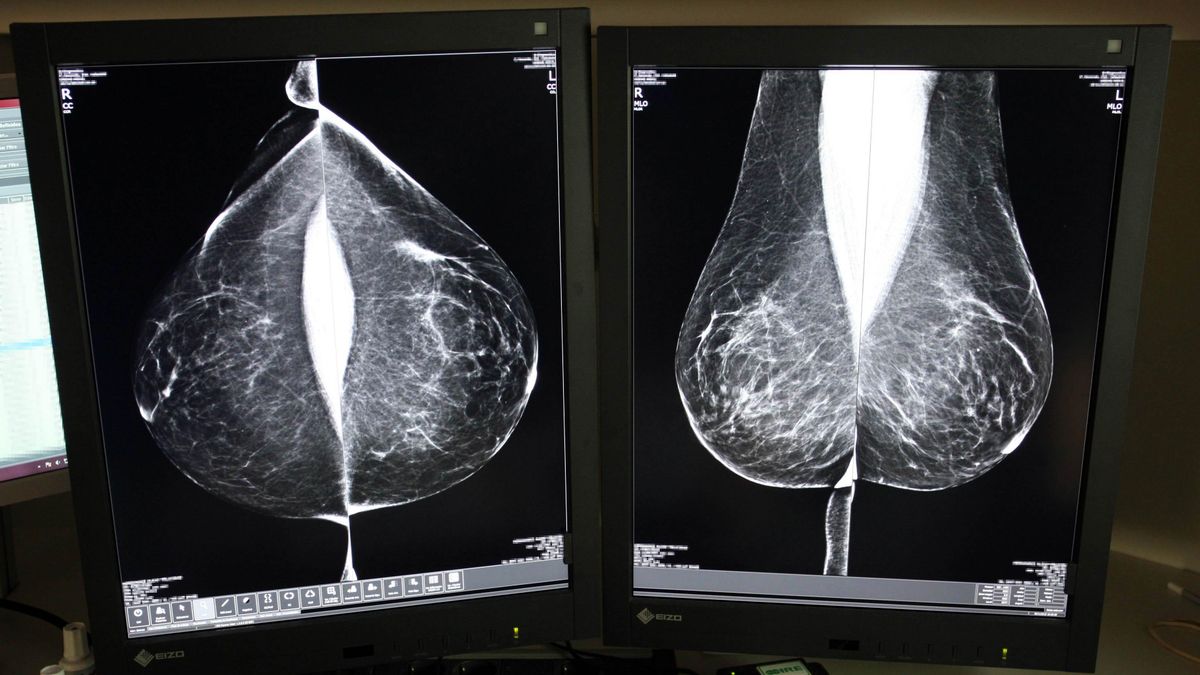

Estudio una mamografía digital, en el servicio de mamografías del Hospital Río Hortega de Valladolid.

Desde su puesta en marcha en 1992, el programa se basa en el sistema de doble lectura, un protocolo que establece que cada mamografía sea evaluada por al menos dos radiólogos, de forma independiente, aumentando así la fiabilidad de los diagnósticos. Sin embargo, aumenta la carga de trabajo y plazos, motivo por el cual Sacyl ha optado, de nuevo, por externalizar el servicio al que el año pasado dedicó casi cuatro millones.